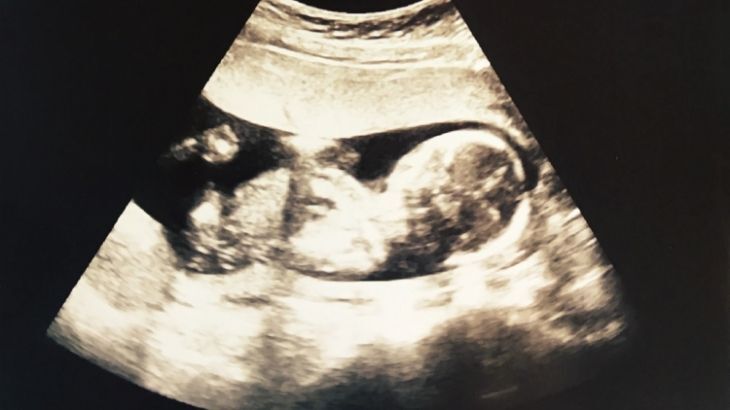

Hamileliğin 16. haftasında bebek hızla gelişmeye devam eder. Bebek rahim içinde serbestçe hareket edebilir, baş pozisyonu değişkendir. Gözleri yavaş yavaş hareket eder, kulaklar ise son pozisyonlarına ulaşmak üzeredir. Bebeğin derisi hala çok incedir ve yarı saydam yapıdadır.

Uzuv hareketleri daha koordineli bir hale gelir ve hareketler ultrason muayeneleri sırasında görülebilir. 16 hafta gebelik döneminde bebeğin hareketleri, anne tarafından hissedilmeyecek kadar düşük şiddettedir.

Gebeliğin ikinci üç aylık dönemi (13–27. haftalar) fetüsün hızlı gelişim gösterdiği bir dönemdir. 16 hafta gebelik döneminde bebeğin cinsiyeti, bebeğin anne karnındaki pozisyonu ve hareketlerine bağlı olarak ultrason muayenesi ile büyük ölçüde belli olabilir. Daha kesin bir sonuç için 18-22. haftalar arasında yapılan detaylı ultrason tercih edilir.

Gebeliğin 16. haftasında bebek zaten başlamış olan kas hareketlerini daha koordine şekilde sürdürür. Tekme atma, dönme ve esneme gibi hareketler ultrasonda görülebilir. Ancak bebeğin hareketleri çok hafif olduğundan anne adayı belirgin biçimde hissedemeyebilir.

İkinci üç aylık dönemde yani gebeliğin 16. haftasında bebeğin cinsiyeti ultrason ile görülebilir. 16 haftalık gebelik döneminde genital organlar belirgin hale geldiği için doktorunuz tarafından daha doğru bir tahmin yapılabilir. Ancak bebeğin duruş pozisyonu veya hareketliliği cinsiyetin net olarak görülmesini zorlaştırabilir.

16 haftalık gebelik ultrason muayenesinde bebeğin yüz hatları ve uzuvları belirgin bir biçimde görülür. Bebeğin başı, omurgası, kalbi ve iç organları incelenebilir. 16. haftada bebeğin cinsiyeti ultrason ile tespit edilebilir.